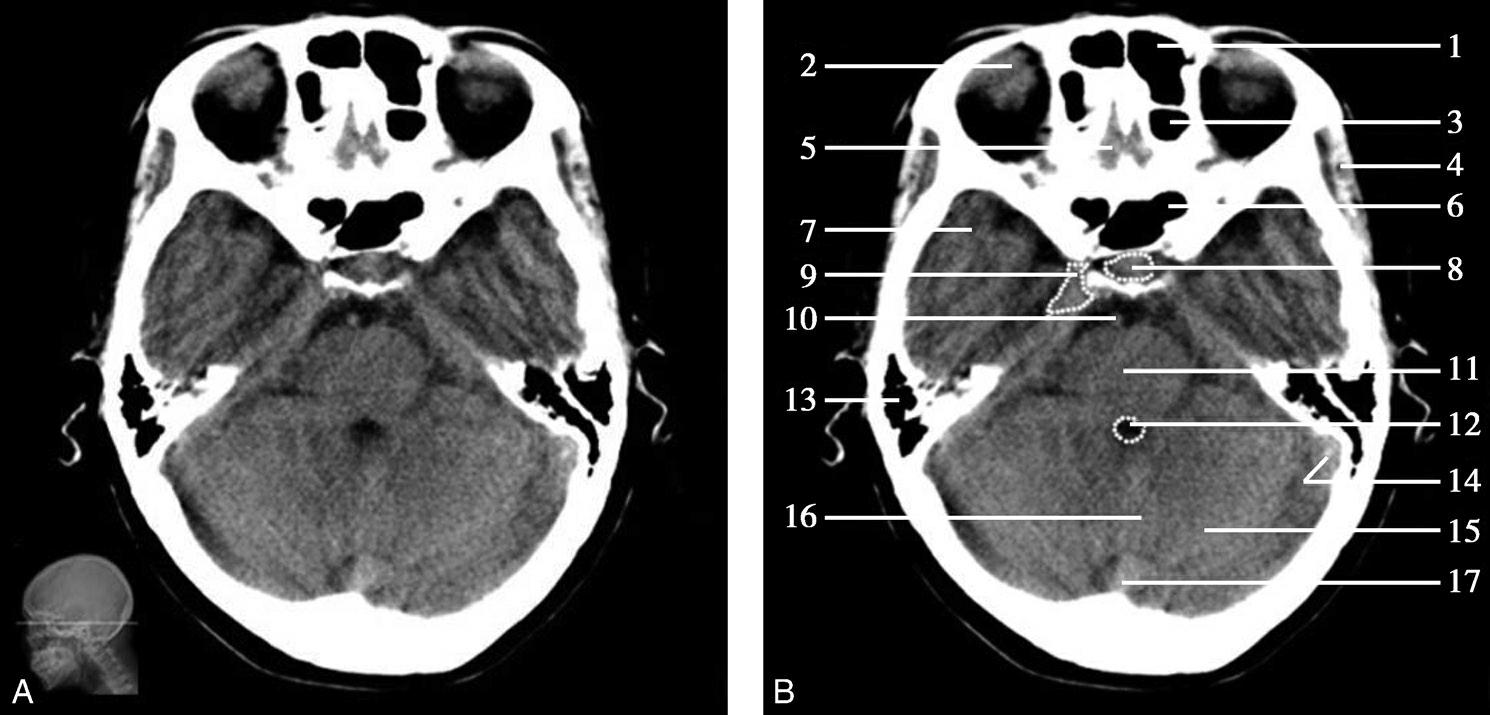

图1-2-2 颅底层面(骨窗)

A.横断面;B.横断面标注

1.鼻骨;2.筛窦纸板;3.颧骨眶突;4.翼腭窝;5.蝶骨大翼;6.卵圆孔;7.破裂孔;8.颞骨颧突;9.棘孔;10.斜坡;11.颞骨岩部;12.乳突;13.颈静脉孔;14.枕乳突缝;15.枕骨;16.枕内隆凸

层面前部呈开口向前的“V”字形,正中为鼻中隔,向两侧依次为筛窦和眼眶,眼眶内前部为眼球,后部为眶脂体。翼腭窝位于眼眶后部,窝内含有脂肪并有上颌神经通过。层面中部为蝶骨体,蝶骨体中部可见含气蝶窦,蝶窦后方为枕骨基底部,两者呈前后关系,其上面构成斜坡。蝶窦两侧为蝶骨大翼,其后外侧缘处由前向后可见卵圆孔和棘孔,分别有下颌神经和脑膜中动脉通过。斜坡外侧、岩骨尖前方为破裂孔。蝶骨大翼与眶外侧壁的颧骨借颧弓相连,颧弓和蝶骨大翼之间有咬肌及颞肌。层面中部外侧为外耳道。颞骨岩部呈“八”字形,相互之间借破裂孔软骨、蝶岩软骨结合和岩枕软骨结合连接。岩部后外侧的乳突部内可见乳突小房,乳突部与枕骨相接。岩骨后部可见颈静脉孔,内有颈内静脉、舌咽神经、迷走神经和副神经通过。层面后部为颅后窝,其内可见延髓,延髓前方为延髓前池,内有椎动脉,后外侧为小脑半球下部,后方为第四脑室、小脑扁桃体及小脑蚓部。